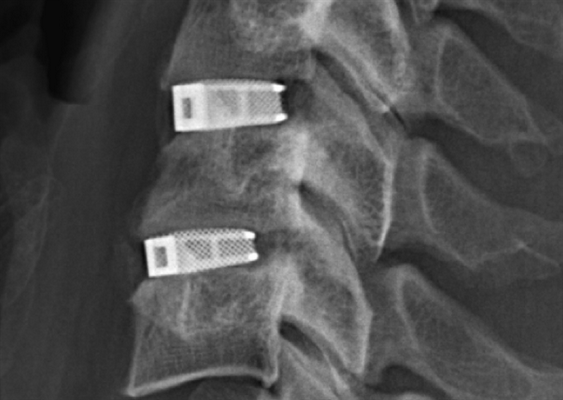

В большинстве случаев проблемный сегмент стабилизируют с помощью металлоконструкций, чаще представленных транспедикулярными системами и пластинами с винтами из высокотехнологичных сплавов металла. В хирургии такая техника называется инструментацией позвоночника. Кроме металлоконструкций, для стабилизации также могут быть применены полимерные устройства, сделанные, например, из углеводородного волокна или резорбирующегося высокомолекулярного биополимера. К отдельной разновидности стабилизирующих вмешательств, которые не причисляют к инструментации, относят установку кейджей имплантатов межпозвоночных дисков.

Кейджы межпозвоночных дисков поясничного отдела.